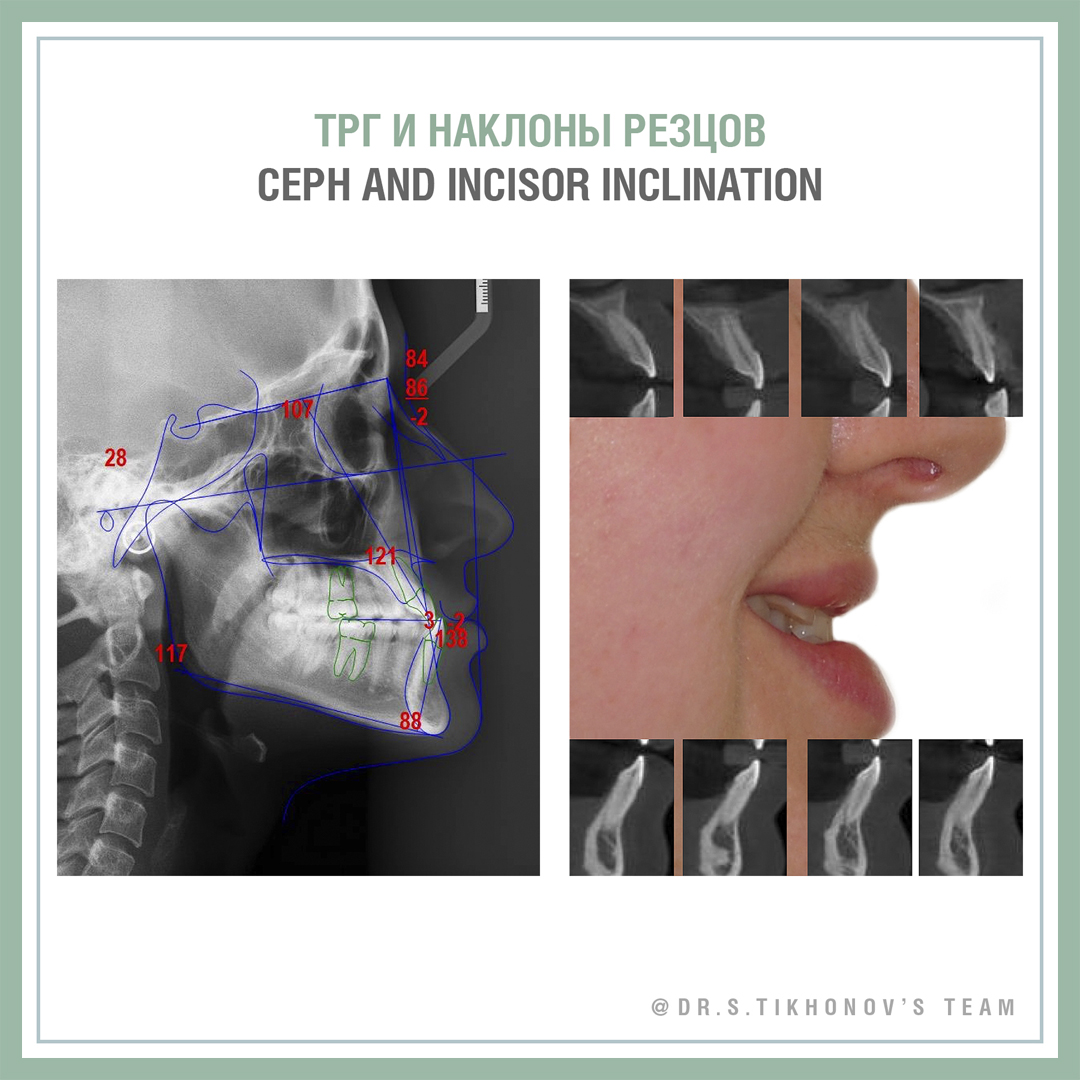

Конечно, я пару раз показывал ее на семинарах, но не все были, не все помнят. Взрослая, с мезиальным прикусом, беспокоит клык и обратное перекрытие, на лицевые признаки жалоб нет. Подробнее диагностическая информация на слайдах.

Сложность тут не только в мезиальном прикусе и перекрытии, но и в очень сильном дефиците места для 13. В Школе мы обсуждаем 5 способов создания места. Интересно, какие подходят здесь?

28 y.o., skeletal class 3, chief complaints: 13, anterior cross bite, facial appearance is ok! Please, share your Tx options in comments! Don’t be shy! This is the training account!